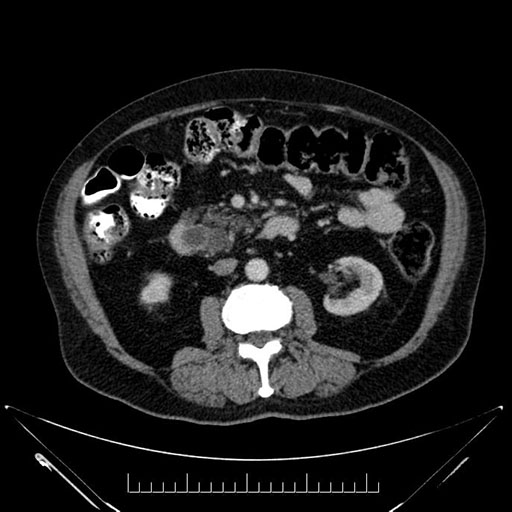

Imaging Analysis

Look through the patient's CT scan to identify any areas of concern for the necessary procedure.

Based on your CT findings, which issue(s) would give reason for "planned slowing down moment(s)" in this case?

Considering a standard Whipple procedure, what step(s) of the operation would you do differently in this case?